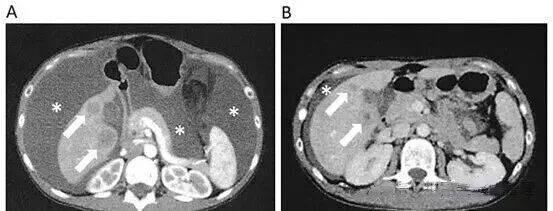

原发肿瘤缩小,多发转移消失:治疗进行到第 142 天时,PET-CT 检查显示,患者体内的肺转移和腹膜播散情况已经消失,肝转移和原发性病变也明显缩小。